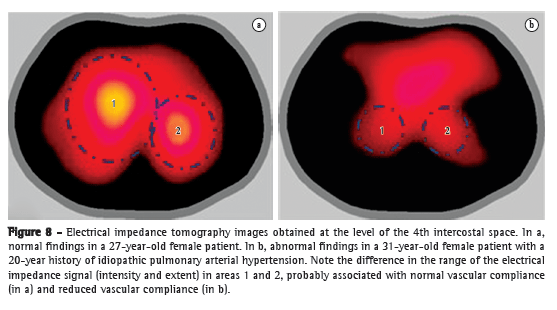

Chest X-ray changes are seen in more than 85% of patients with a confirmed diagnosis of PH.(4) The major changes found include increased pulmonary artery diameter at the hilar level, in 78% of cases (Figure 1); peripheral tapering of vessels, in 62%; and hyperlucent lung periphery, in 9% (Figure 2). The pulmonary artery diameter at the hilar level can be determined by measuring the interlobar artery diameter. The maximum transverse diameter of the right interlobar artery, as measured from its lateral aspect to the air column of the intermediate bronchus, is 16 mm in men and 15 mm in women.(5) Because of the difficulty in assessing the left pulmonary artery by posteroanterior chest X-ray, the vessel should be assessed by lateral X-ray, beginning at the circular transparency created by the left upper lobe bronchus (which is visualized as being telescoped) and extending to the posterior margin of the vessel saddling the bronchus (Figure 1). The maximum limit of normality is 18 mm. A hilar-thoracic index (sum of the diameters of the pulmonary hila divided by that of the chest) above 38% is classically described, being present in approximately 75% of patients with PH (Figure 1).(6) Vascular calcification, usually located in the pulmonary artery trunk (PAT) or in its hilar branches, is rarely detected. This change is most commonly associated with congenital heart diseases and chronic central embolism.

Chest X-ray can facilitate the differential diagnosis with pulmonary parenchymal disease, heart failure, COPD, and kyphoscoliosis, as well as raising the suspicion of pulmonary thromboembolic disease when there are findings of oligemia, multiple areas of consolidation suggestive of pulmonary infarction, or asymmetry among the major pulmonary arteries (Figure 2).(7)